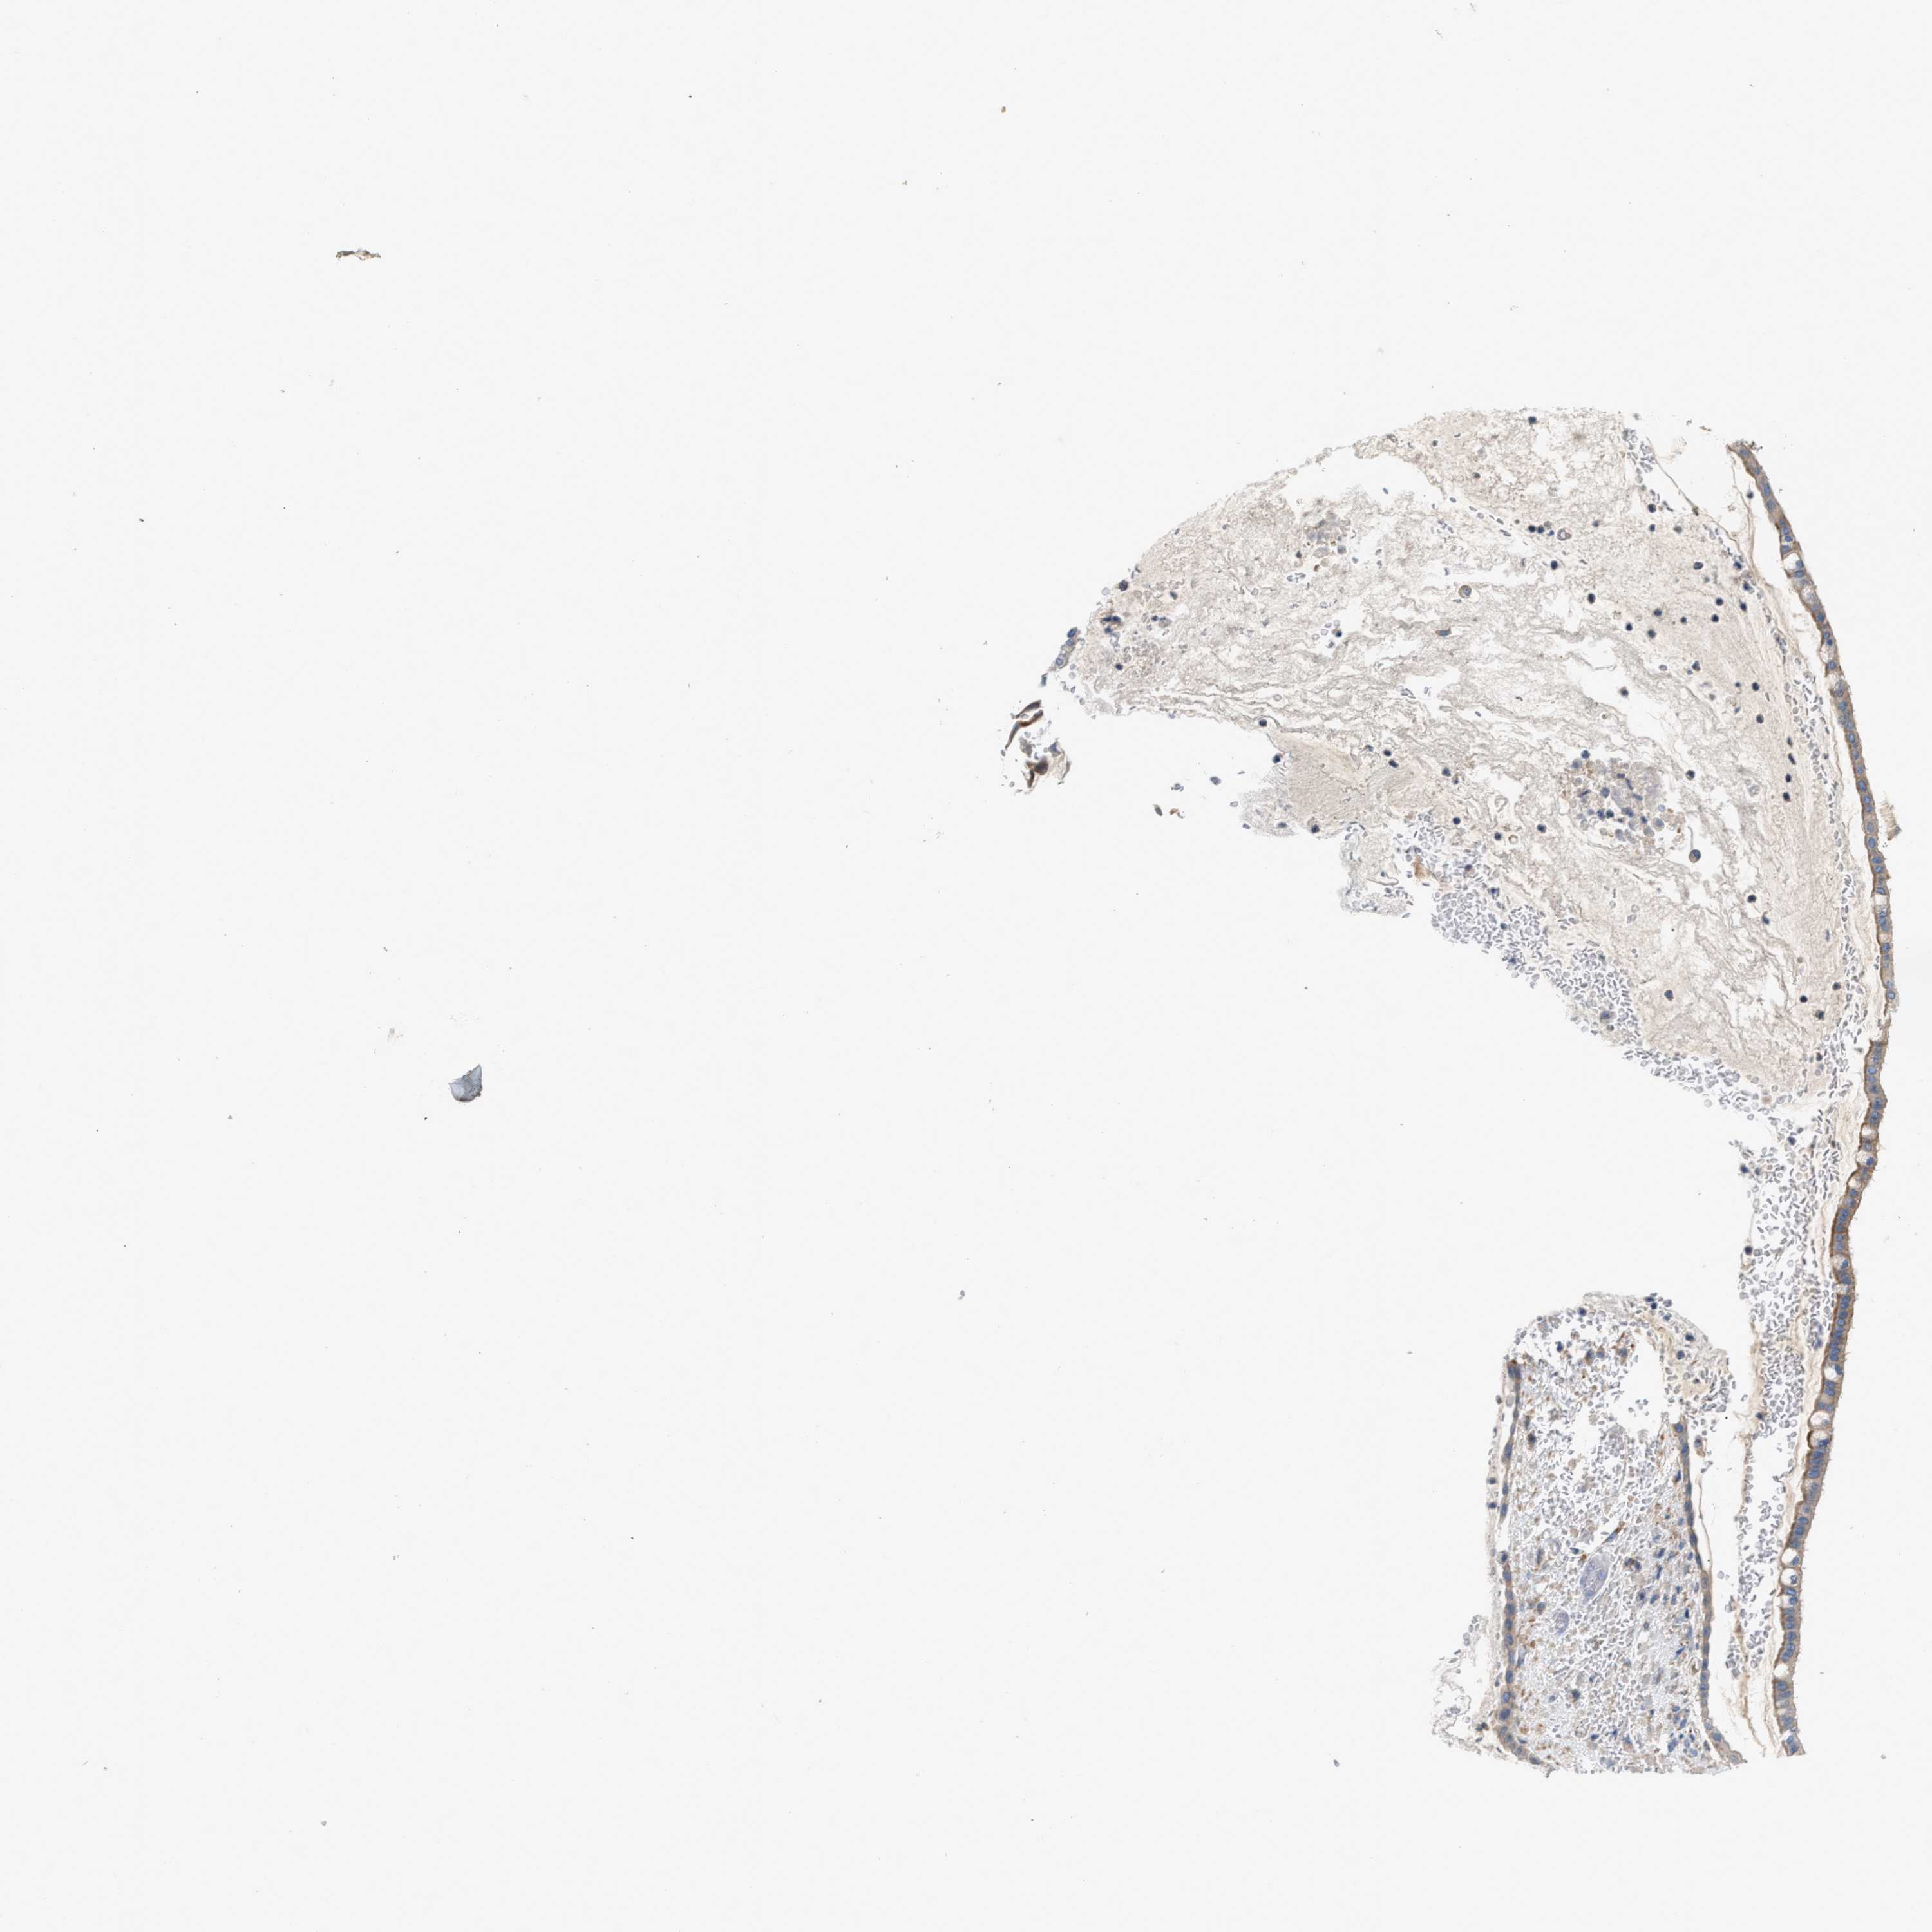

OVARIAN CANCER - Protein expressioni

A mouse-over function shows sample information and annotation data. Click on an image to view it in a full screen mode. Samples can be filtered based on level of antibody staining by selecting one or several of the following categories: high, medium, low and not detected. The assay and annotation is described here.

Note that samples used for immunohistochemistry by the Human Protein Atlas do not correspond to samples in the TCGA dataset.

Antibody stainingi

Antibody staining in the annotated cell types in the current human tissue is reported as not detected, low, medium, or high, based on conventional immunohistochemistry profiling in selected tissues. This score is based on the combination of the staining intensity and fraction of stained cells.

Each image is clickable and will lead to virtual microscopy that enables deeper exploration of all samples and also displays staining intensity scores, fraction scores and subcellular localization as well as patient and tissue information for each sample.

Antibody HPA020653

Staining

High

Medium

Low

Not detected

Intensity

Strong

Moderate

Weak

Negative

Quantity

>75%

75%-25%

<25%

None

Location

Nuclear

Cytoplasmic/membranous

Cytoplasmic/membranous,nuclear

Cystadenocarcinoma, serous, NOS

Carcinoma, endometroid

Cystadenocarcinoma, mucinous, NOS

Carcinoma, NOS